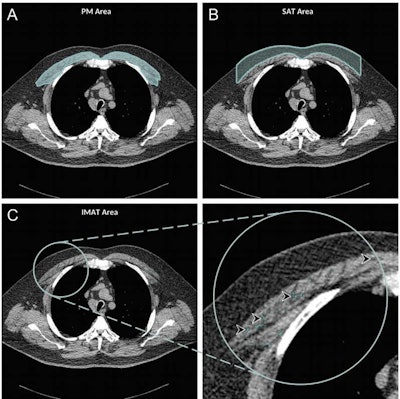

Axial chest CT examination in a 54-year-old participant. (A) On the axial noncontrast chest CT image, the pectoralis muscle (PM) area was segmented and measured in the section above the aortic arch. (B) The subcutaneous adipose tissue (SAT) area as the area between the pectoralis muscle and the skin surface on the same section was also measured and the attenuation of pixels in the subcutaneous adipose tissue area was used to determine the individualized threshold for the intermuscular adipose tissue. (C) The intermuscular adipose tissue within the pectoralis muscle was segmented as the areas with Hounsfield units below this threshold for the intermuscular adipose tissue (IMAT) (arrowheads). Images and caption courtesy of the RSNA.

Axial chest CT examination in a 54-year-old participant. (A) On the axial noncontrast chest CT image, the pectoralis muscle (PM) area was segmented and measured in the section above the aortic arch. (B) The subcutaneous adipose tissue (SAT) area as the area between the pectoralis muscle and the skin surface on the same section was also measured and the attenuation of pixels in the subcutaneous adipose tissue area was used to determine the individualized threshold for the intermuscular adipose tissue. (C) The intermuscular adipose tissue within the pectoralis muscle was segmented as the areas with Hounsfield units below this threshold for the intermuscular adipose tissue (IMAT) (arrowheads). Images and caption courtesy of the RSNA."Compared with subcutaneous adipose tissue quantification, intermuscular adipose tissue may be a better marker for predicting all-cause mortality in patients with COPD ... [in part because] the intermuscular adipose tissue index is an indicator of other underlying comorbidities (e.g., diabetes and hypertension) and may predict the all-cause mortality better," the authors wrote.